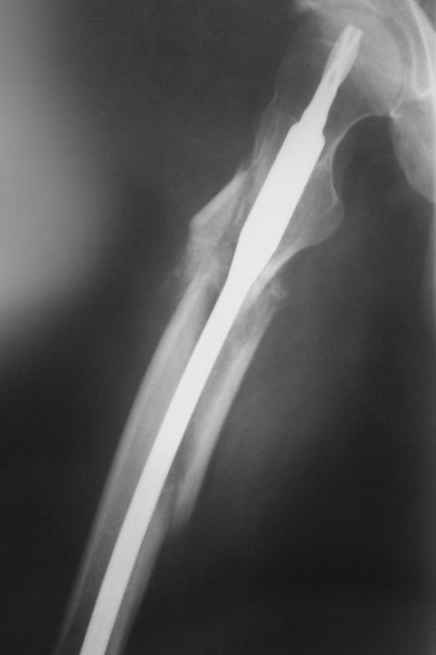

Alexander Chelnokov> Практически единственное, что делает необходимым разрез для манипуляций с промежуточным отломком бедренной кости - это его "застегивание" в илиотибиальном тракте по типу пуговицы в петле.

На операции я оставил осколок в области приводящих мышц бедра (ни пальпаторно, ни спицей сдвинуть не смог, "заклинило" насмерть). Фото спустя 2 месяца после операции (PFN).

Только сейчас пациент стал более или менее активным. Сразу после операции жалобы на сильные боли при отведении и приведении бедра в области отломка. Сейчас отломок пальпируется и пациент испытывает дискомфорт, хотя амплитуда движений объективно прогрессирует.

Теперь думаю, надо все-таки было через минидоступ или резецировать, либо репонировать. Обычно при таких операциях уже на 2-й день пациенты на костыли и по отделению, а у этого задержка длительная получилась. Только спустя 2 недели кое-как на костыли взобрался. Ни отека, никакой неврологии, только эти боли в области осколка.